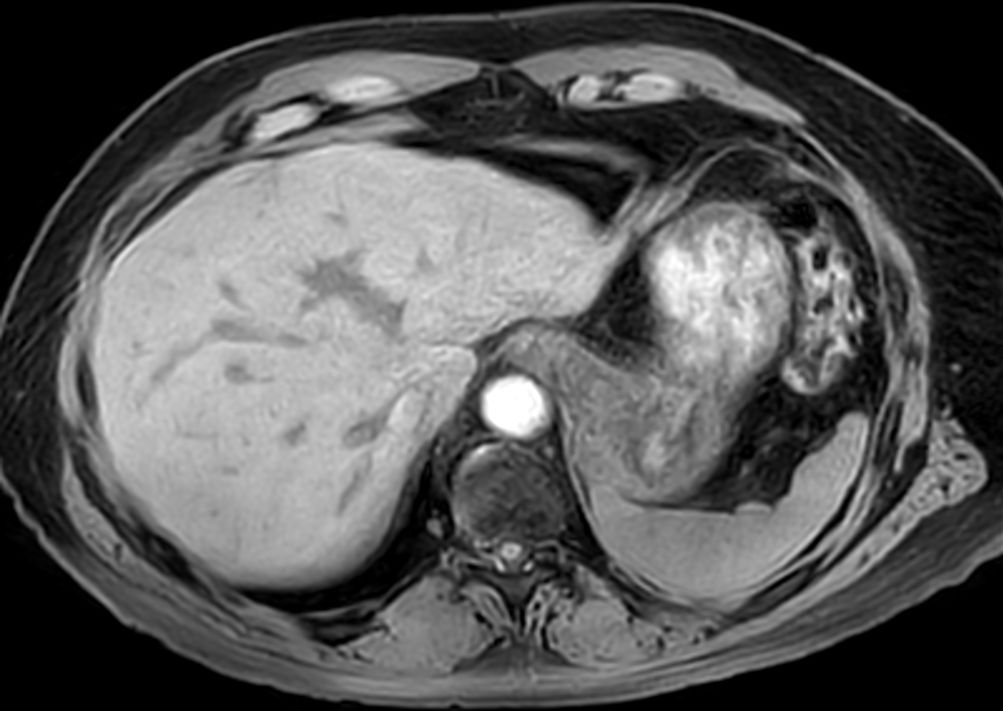

Axial T2w TSE mDIXON (out-phase)SmartSpeed Diffusion